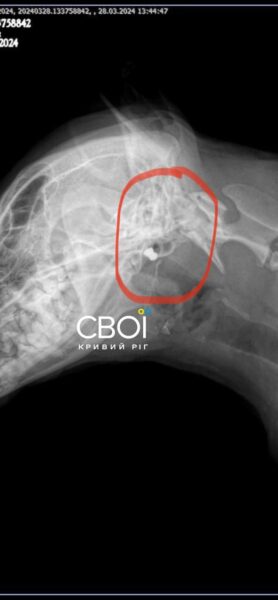

Ветеринар призначив лікування для Баті. Одна з куль застрягла у голові тварини, інша – біля шлунка. Дістати їх, аби не нашкодити собаці, неможливо.